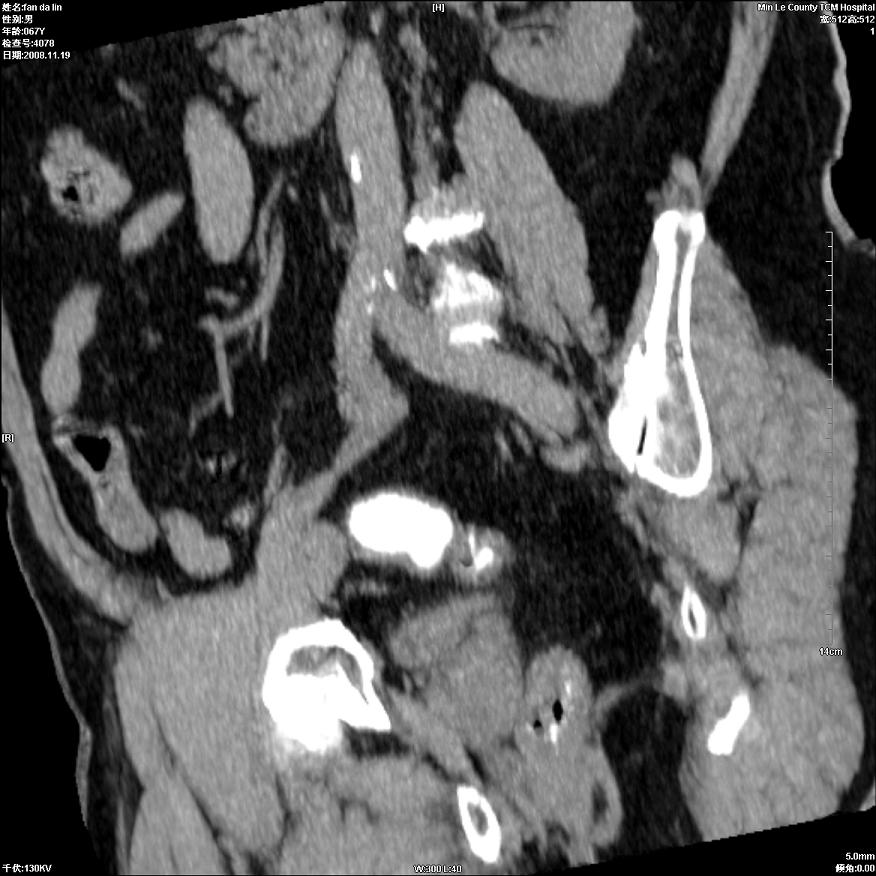

标题: CT16698:M67Y,看看直肠下端是不是病变 [打印本页]

标题: CT16698:M67Y,看看直肠下端是不是病变

粘膜皱壁,不除外内痔

直肠及乙状结肠管壁均增厚,考虑炎症.

直乙交界处肠壁不规则增厚,还是做个肠镜吧

只是肠壁局限性增厚,但难说明问题。